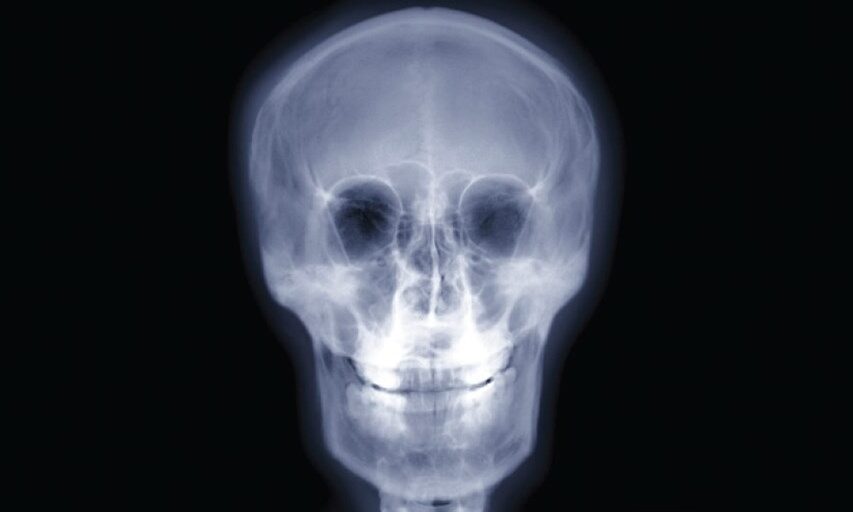

Medical X-rays produce highly detailed images of tissues and structures inside the body. If X-rays traveling through the body also pass through an X-ray detector on the other side of the patient, an image will be formed that represents the shadows formed by the objects inside the body.

Radiological density, a key concept in radiography, is a measure of a material’s resistance to the passage of X-rays. It is determined by both the density and the atomic number (the number of protons in an atom’s nucleus) of the materials being imaged. For example, structures such as bone contain calcium, which has a higher atomic number than most tissues. Because of this property, bones readily absorb X-rays and, thus, produce high contrast on the X-ray detector.

As a result, bony structures stand out distinctly, appearing whiter than other tissues against the black background of a radiograph. This stark contrast is a key feature of radiographs. Conversely, X-rays pass more readily through less radiographically dense tissues, such as fat and muscle, as well as through air-filled cavities, such as the lungs. These structures appear in shades of gray on a radiograph, creating a nuanced visual representation of the body’s internal structures.